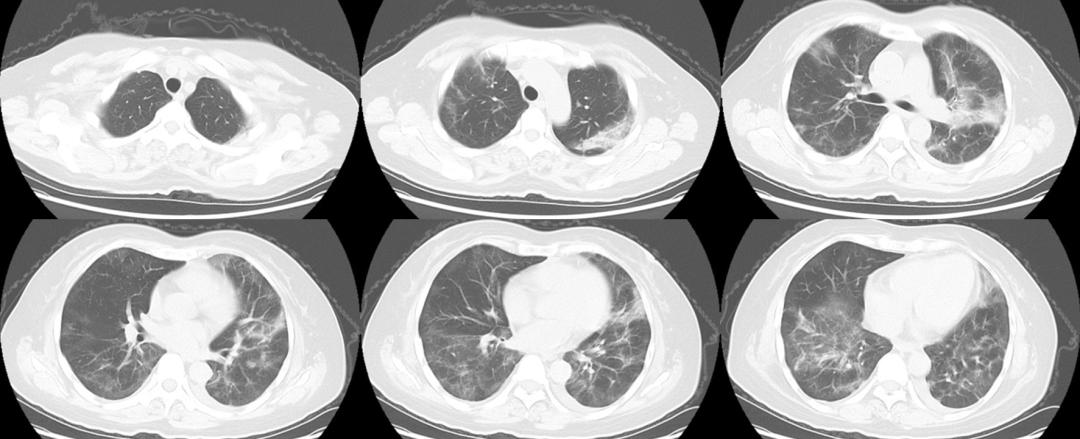

图4 胸部CT平扫(2023年3月13日)

结合影像学游走性肺炎、咽拭子及BALF病原学结果,考虑为新冠病毒持续感染。2023年3月7日起予奈玛特韦/利托那韦口服抗病毒治疗,3月8日患者体温恢复正常、咳嗽及气短症状逐渐缓解,吸空气血氧饱和度恢复至96%以上。2023年3月13日复查胸部CT:双肺病变较前减少。